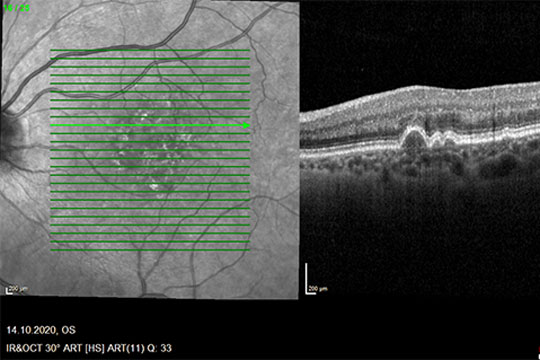

- Grundlagen der augenheilkundlichen Funktionstestung und Bildgebungsverfahren